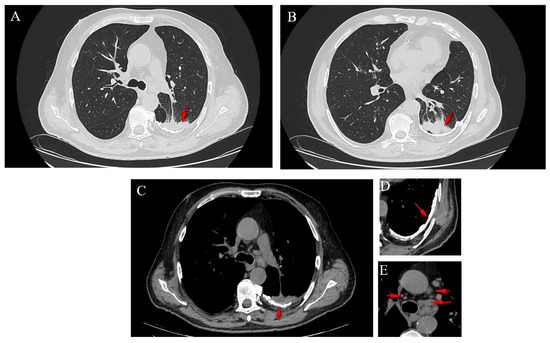

2.2. Thoracic Computed Tomography